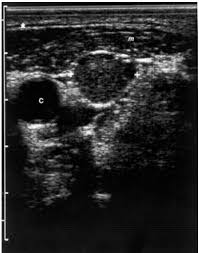

A solid one is more likely to have cancerous cells, but you'll still need more tests to find out. They may put a small, thin camera down your throat to look for problems, a procedure called a laryngoscopy. Ultrasound of the thyroid gland is necessary in the presence of the patient's complaints of a feeling of lump in the throat and difficulty swallowing, an unreasonable cough, increased nervousness and excitability, sleep disturbance, palpitations and tremors of hands, swelling, weight loss, prolonged subfebrile condition. What does ovarian cancer look like on an ultrasound is not an easy question to answer. Throat cancer refers to cancer of the voice box, vocal cords, and other parts of the throat, such as the tonsils and the oropharynx. Ultrasound technology is an important way to diagnose various conditions. For example, throat cancer pictures below are three stages of cancer of the tonsils. Doctoroncall is a platform where you can ask more about your health conditions. Thus, an ultrasound can detect a liver cancer when aided by other diagnostic tests. A small transducer (probe) both transmits sound waves into the body and records the waves that echo back. The cells are then looked at closely in the lab. Connect by text or video with a u.s. Some common causes of enlarged lymph nodes are infections such as a cold, ear infection, strep throat or a more systemic condition like lupus or hiv.

Throat Cancer Photos And Premium High Res Pictures Getty Images from media.gettyimages.com Ultrasound exposes you to no radiation whatsoever. What does eye cancer look like. For instance, voice changes may be a sign of laryngeal (voice box) cancer, but they would rarely indicate cancer of the pharynx. My 3.8 year old's neck ultrasound shows chain of lymph nodes bilaterally with largest on right 14mm by 6mm and largest on left 13mm by 6mm,the left one is there since a year.few intraparotid largest 5mm.thyroid & both submandibular normal. Needle biopsy is only indicated if there is a mass within the thyroid goiter which is suspicious for malignancy. As they grow, they can form into a tumor and crowd out normal and healthy cells. May 22, 2021 uncategorized uncategorized Ultrasound technology is an important way to diagnose various conditions.

My 3.8 year old's neck ultrasound shows chain of lymph nodes bilaterally with largest on right 14mm by 6mm and largest on left 13mm by 6mm,the left one is there since a year.few intraparotid largest 5mm.thyroid & both submandibular normal. However, thyroid cancer and most benign nodules can look the same on the ultrasound. Home / uncategorized / what does thyroid cancer look like on ultrasound; If the cancer cells look like they might have come from the larynx or hypopharynx, an endoscopic exam and biopsy of these areas will be needed. What does ovarian cancer look like on ultrasound ? Your voice box sits just below your throat and also is susceptible to throat cancer. Ultrasound imaging can help determine the composition of lump, distinguishing between a cyst and a tumour. What does vulvar cancer look like. Throat cancer most often begins in the flat cells that line the inside of your throat. Needle biopsy is only indicated if there is a mass within the thyroid goiter which is suspicious for malignancy. Doctoroncall is a platform where you can ask more about your health conditions. A primary cancer of the lymphatic system is called lymphoma. An ultrasound is a painless procedure that uses sound waves to generate images of the inside of your body.